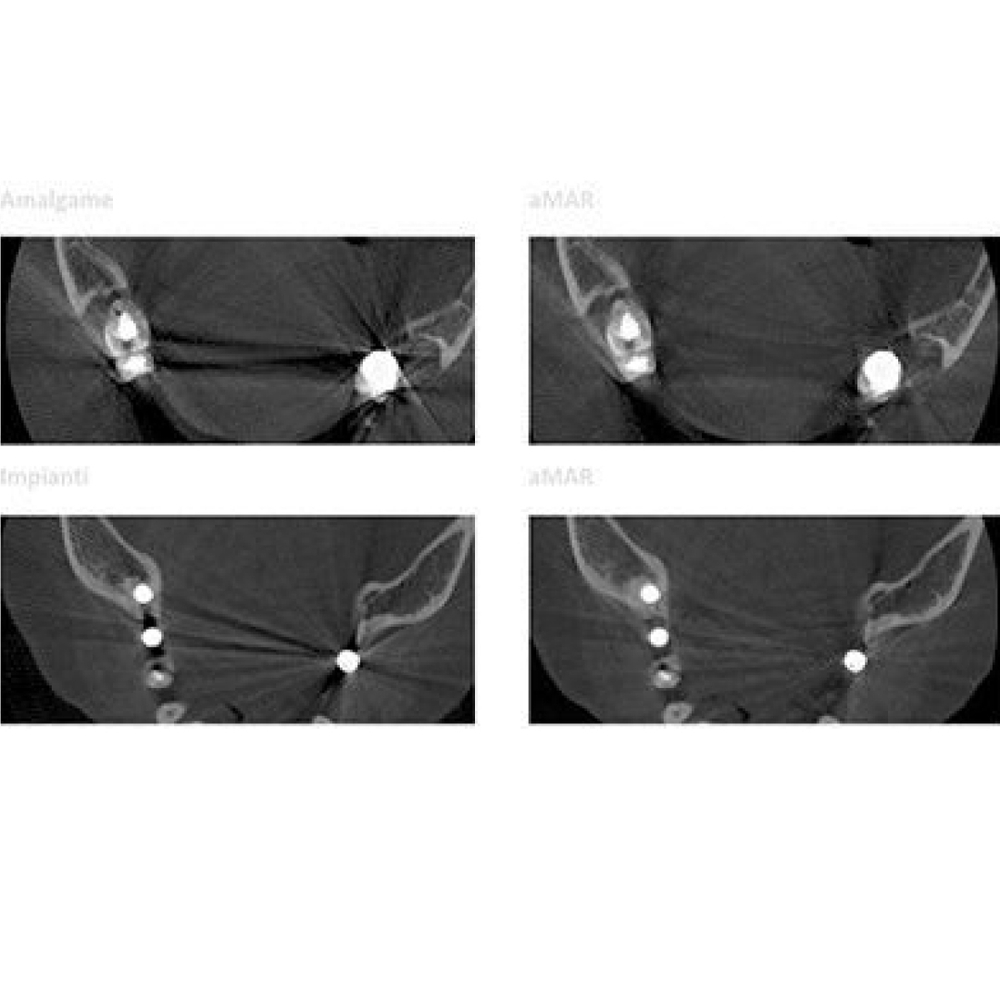

Программное обеспечение NewTom NNT предлагает все функции, необходимые для выполнения, обработки, вывода на экран и передачи 2D и 3D результатов обследования. NNT также предоставляет различные режимы и функции приложения, специально предназначенные, чтобы планировать лучшее лечение в области имплантологии, эндодонтии, пародонтологии и рентгенографии, а также в челюстно-лицевой хирургии.

Совершенство в 3D

NewTom GO генерирует выдающиеся объемные изображения и для каждого FOV в диапазоне от 6х6 до 10х10 см. Выбор из 3 протоколов позволяет адаптировать требуемую дозу рентгеновского излучения к конкретным потребностям: от очень низкой для быстрого сканирования, необходимого при последующих хирургических проверках, до регулярной для планирования лечения, до очень высокого уровня детализации для анализа микроструктур.